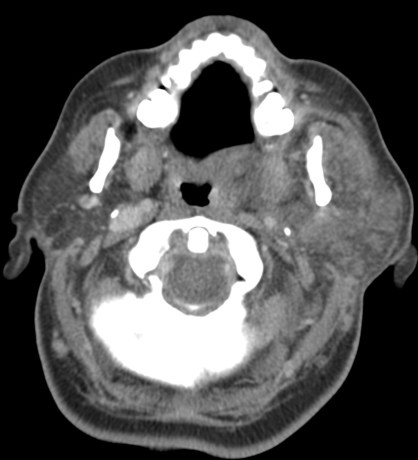

Amigdalitis, Absceso periamigdalino y parafaríngeo:

La clínica no permite diferenciar con exactitud entre celulitis y absceso y no permite determinar con exactitud la extensión del proceso. Clínicamente se sospecha un absceso cuando existe dolor en región cervical y amígdalas que empeora progresivamente a pesar de antibióticoterapia oral, fiebre persistente, odinofagia, voz gangosa, adenopatías cervicales dolorosas y en algunas ocasiones trismus.

Hallazgos:

- Aumento de tamaño de las amigdalas (amigdalas «besándose») con aumento de realce tras tras aplicación de contraste iv.

- En fases avanzadas surgen hipodensidades parenquimatosas o colecciones líquidas debido al edema y la celulitis existente.

- Un absceso periamigalino se diferencia de la celulitis porque presenta una licuefacción/colección central con anillo periférico realzado que puede o no presentar burbujas de aire en su interior. Un absceso de morfología irregular indica estadio más evolucionado.

- El absceso puede extenderse al espacio parafaringeo, constituye el 9% de todas las masas parafaríngeas.

- La distinción entre celulitis y absceso es importante en lo que al tratamiento se refiere. Si existe una colección drenable, la aspiración es el tratamiento requerido. Una colección con anillo periférico realzado, es compatible con absceso drenable en el 63-77% de los casos, población pediátrica y adulta incluida.

- Puede observarse agrandamiento y realce de la úvula.

- Es frecuente identificar adenopatías cervicales.

- Es frecuente observar una mala delimitación de los tejidos blandos adyacentes y las adenopatías cervicales.

- Una vez que la infección ha remitido, pueden quedar calcificaciones residuales en la amígdala.